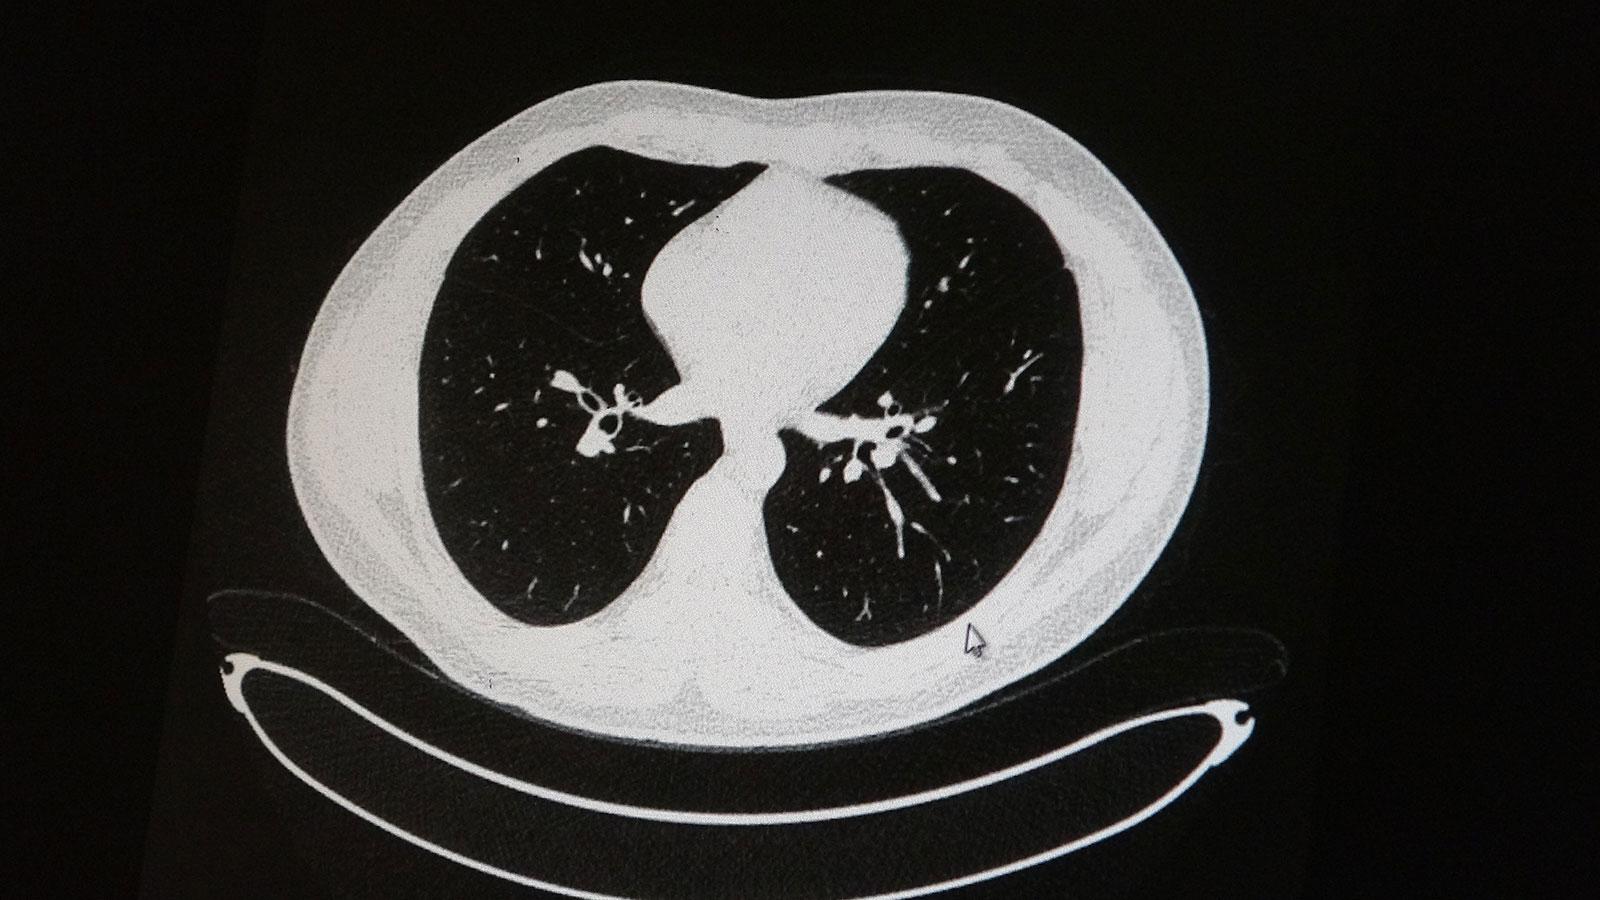

Elazığ’da öksürük, halsizlik, yorgunluk ve çabuk yorulma gibi şikayetlerle hastaneye başvuran ve koronavirüs tespit edilen 2 genç hastadan aşısız olanının tomografi sonuçlarında virüsün akciğerlerde zatürreye sebebiyet verdiği görüldü. Aynı şekilde aşı olup koronavirüs hastalığına yakalanan bir başka genç hastanın bilgisayarlı akciğer tomografisinde akciğerinde herhangi bir sorunun olmadığı belirlendi.

Medical Park Elazığ Hastanesi Göğüs Hastalıkları Uzmanı Dr. Cebrail Azar, geçtiğimiz yıla oranla yoğun bakımda yatan hastaların yaş ortalamasının 65’ten 35’lere kadar düştüğüne dikkat çekti. Genç olduğu halde aşı olmayanlarda hastalığın ağır seyrettiğini ifade eden Uzm. Dr. Azar, “Ben gencim, benim bağışıklık sistemim kuvvetli” diyen genç bir hastanın akciğerlerinde ciddi lekelenmelerin olduğunu ve koronavirüs zatürresi olduğunu gördüklerini belitti. Uzm. Dr. Azar, aynı şekilde aşı olup koronavirüs hastalığına yakalanan bir başka genç hastanın akciğer tomografisinde akciğerde herhangi bir sorunun olmadığını ve hastanın durumunun iyi olduğunu gözlemlediklerini kaydetti. Uzm. Dr. Azar, sürekli şahit oldukları “Keşke biz aşı olsaydık” sözünü bir daha duymamak için herkesi aşı olmaya davet etti.